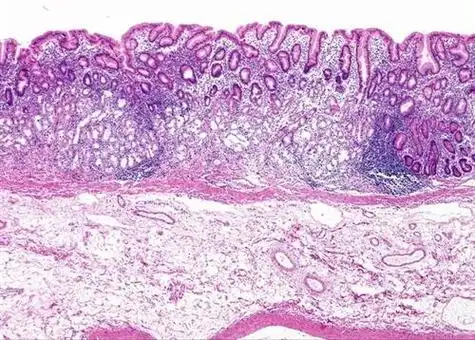

有慢性萎缩性胃炎怎么办